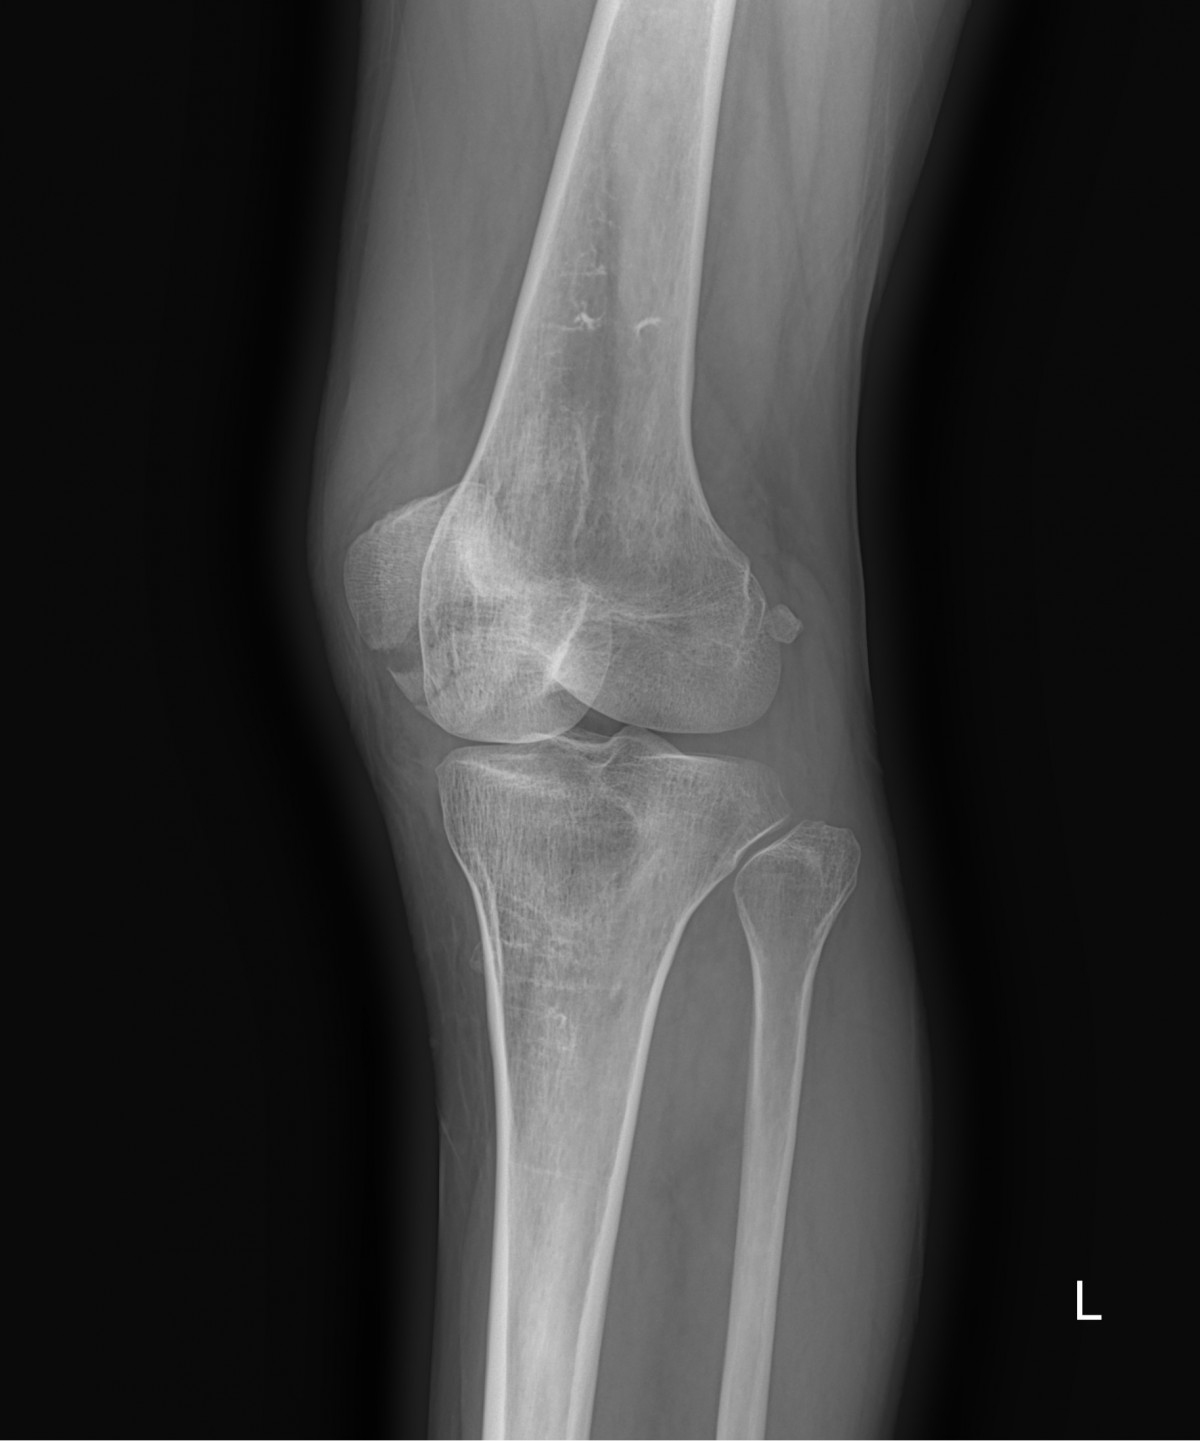

이재상원장님 무릎 골절 수술 고현O 환자

dae765e4d9ac96aee867c9d6292d8784_1758001563_1029.jpg